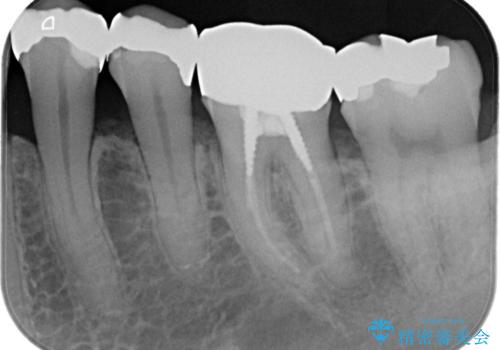

- 金属を外して白い歯を手に入れたいとのことで来院されました。

まとめて治療することで通院回数を減らすことができ、見た目も大変満足していただきました。

根管治療歯は破折防止のため速やかに被せ物が必要になります。